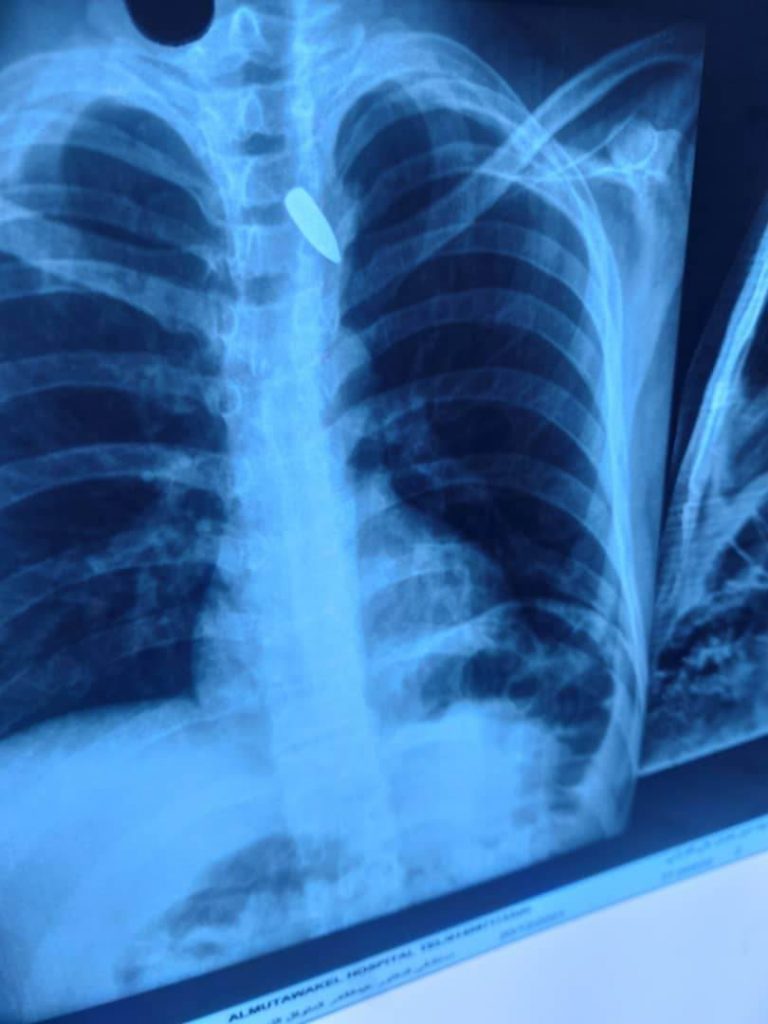

توفيت امرأة وأصيب 32 آخرون في أمانة العاصمة والمحافظات؛ نتيجة الرصاص الراجع، الذي أطلقه عدد من المتهورين احتفالا بفوز المنتخب الوطني للناشئين بكأس غرب آسيا، مساء أمس.

وأوضح المتحدث الرسمي لوزارة الداخلية، العميد عبد الخالق العجري، أن امرأة توفيت في أمانة العاصمة، وأصيب 32 مواطنا في الأمانة وبقية المحافظات، 13 منهم إصابتهم بالغة، وثلاثة في حالة موت سريري، نتيجة إصابتهم بالرصاص الراجع، الذي أطلقه المستهترون الذين لم يلتزموا بتوجيهات وزارة الداخلية، وتحذيرها من إطلاق النار في الهواء، خلال الاحتفال العفوي بفوز المنتخب.